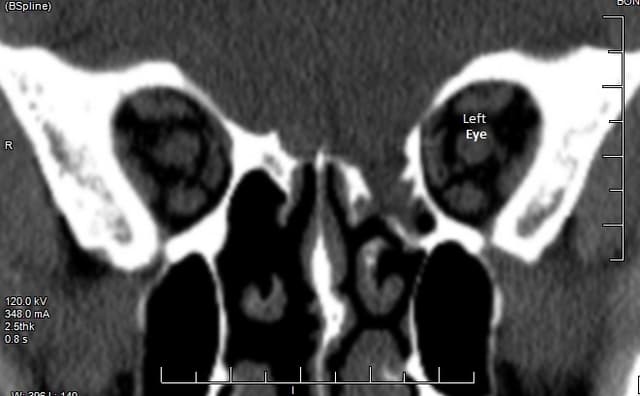

Here is the CAT scan of my injury when it was discovered in 2015. The damage was done to my left side (on the right in this photo).

You can see a bone extending from the right eye socket to the nose with a small ridge on the top that is missing from the left eye.

Just beneath where that should be on the left eye, there are two bone spikes extending into the space. Over the years, the bone tried to repair itself, but the gap was too wide, so the bone grew into bony crystalline reaching into the tissue.

The gray areas are soft tissue. Above the eyes, of course, is brain tissue. The scan shows a mass of tissue that had prolapsed into the sinus cavity below. Those bone spikes were a double-edged sword, as they held the brain in place, but when it slipped, they tore into it as well.

You can see the clear spaces of the sinus below my right eye compared to the tissue-filled sinuses on my left.